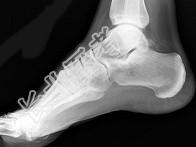

- 单项选择题男,47岁, 关节炎病史20年,结合图像, 最可能的诊断是 ( )

A、类风湿关节炎

B、痛风

C、骨关节结核

D、牛皮癣性关节炎

E、Reiter综合征